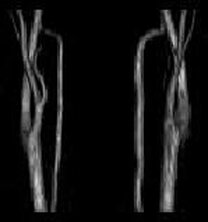

7,MRI検査(頭部の断層撮影,頭部と頚部の血管撮影)

頚動脈エコー